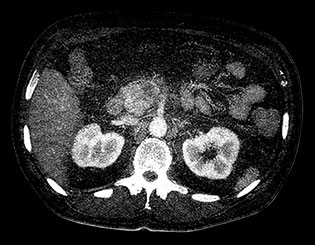

Выполните просмотр требуемой области с помощью нескольких решений благодаря эксклюзивному приложению Spectral Magic Glass для вычленения данных о составе тканей.

Здесь представлена серия изображений, на которых значения воксела обозначают эффективное атомное число. Эффективное атомное число может быть дробным, обозначающим какой-либо элемент, соединение или смесь. Данное число может отличаться от порядкового номера, указанного в периодической таблице. Единица для обозначения — Z.